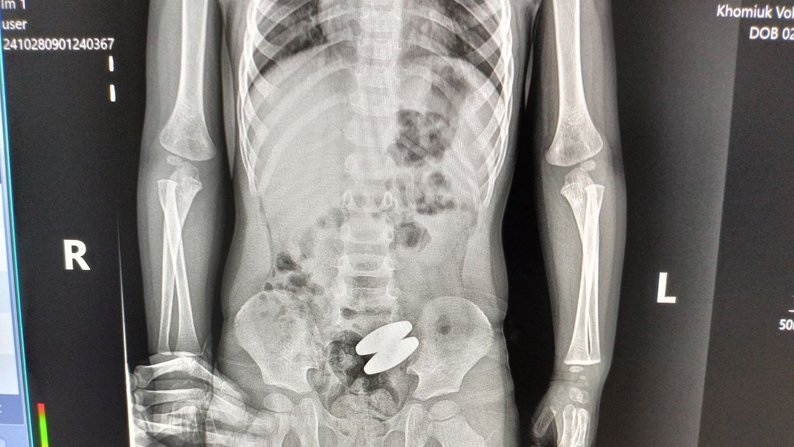

«Ось такі магніти були видалені з кишківника, довжина їх 4 сантиметри, діаметр 1,7 см. Зробити це було лапароскопічно непросто. Коли я витягнув один магнітик, то була думка така, що не варто далі проводити операцію, а залишити й один магнітик вийде сам. Але, зважаючи на те, що він – важкий, і було вирішено операцію продовжити й видалити обоє магнітів», – каже лікар-хірург Василь Никитюк.